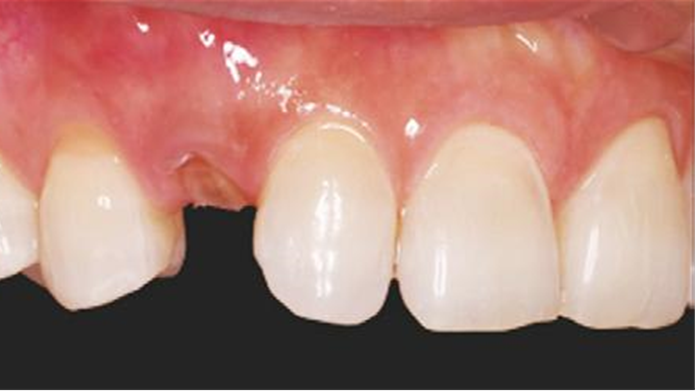

Clinical case: BPET PREDICTABILITY - State-of-the-Art SOCKET SHIELD

- Courtesy of Dr. Howard Gluckman, South Africa -

“AnyRidge is perfect for the anterior esthetic zone due to its strong initial stability & fast osseointegration.

Plus, KnifeThread® ensures space maintenance when using the PET/Socket Shield/Root Membrane Technique, showing excellent bone growth.”